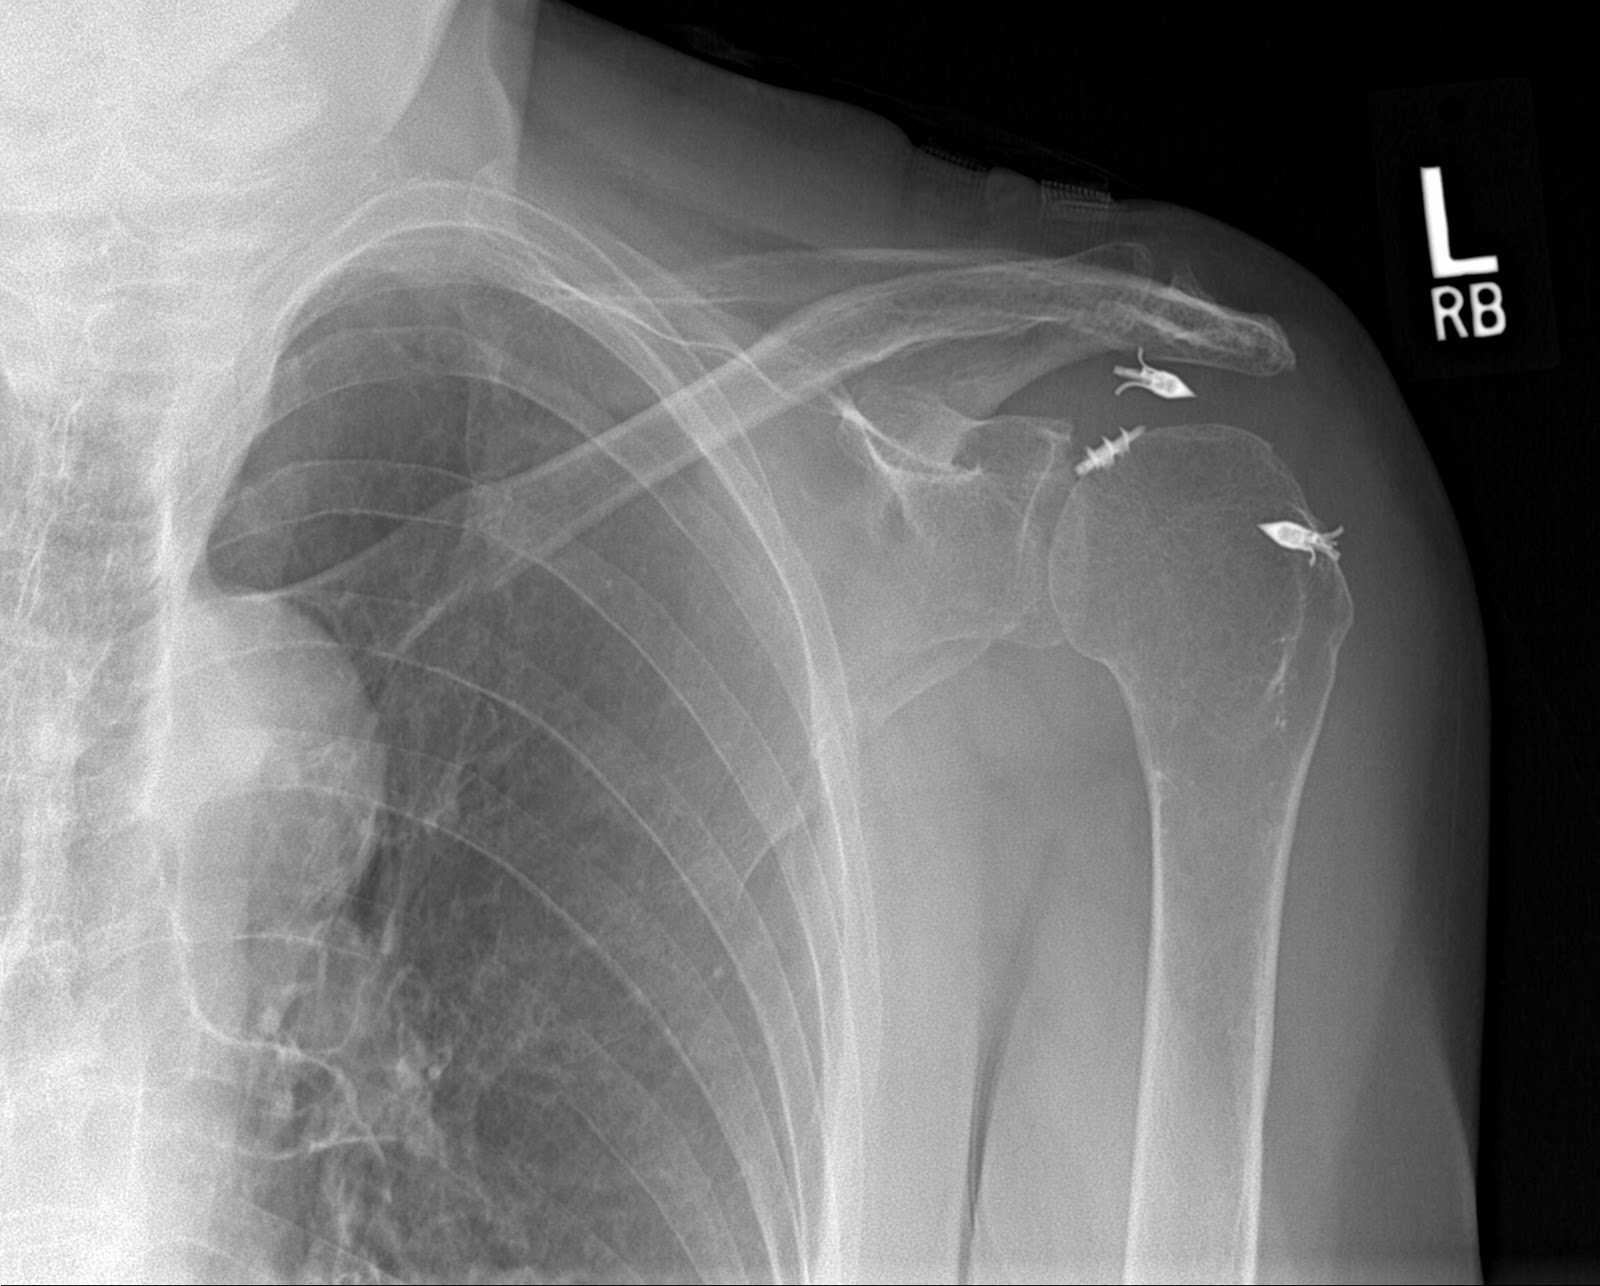

Acute Shoulder Injuries in Adults AAFP